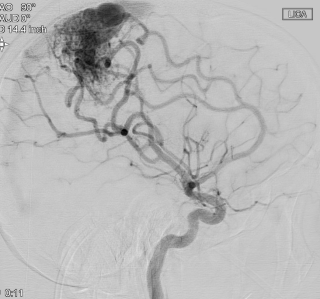

A scan showing the arteriovenous malformation – or AVM – in Kian Ruid’s brain.

An MRI revealed the reason: a rare abnormality in Kian’s brain: an arteriovenous malformation, or AVM — a dangerous tangle of blood vessels that can hemorrhage, causing seizures or stroke-like symptoms.

“AVMs in the brain are urgent because rupture risk rises substantially each year they’re left untreated — for Kian, he was facing a 90% chance that the AVM would rupture during his lifetime,” says Dr. Ducis. “But removing one that is entangled with the brain’s motor center, like in Kian’s case, can be particularly risky.”

The motor cortex controls body movement. Removing even a tiny section can cause permanent loss of function. Kian’s AVM was large and deeply embedded.